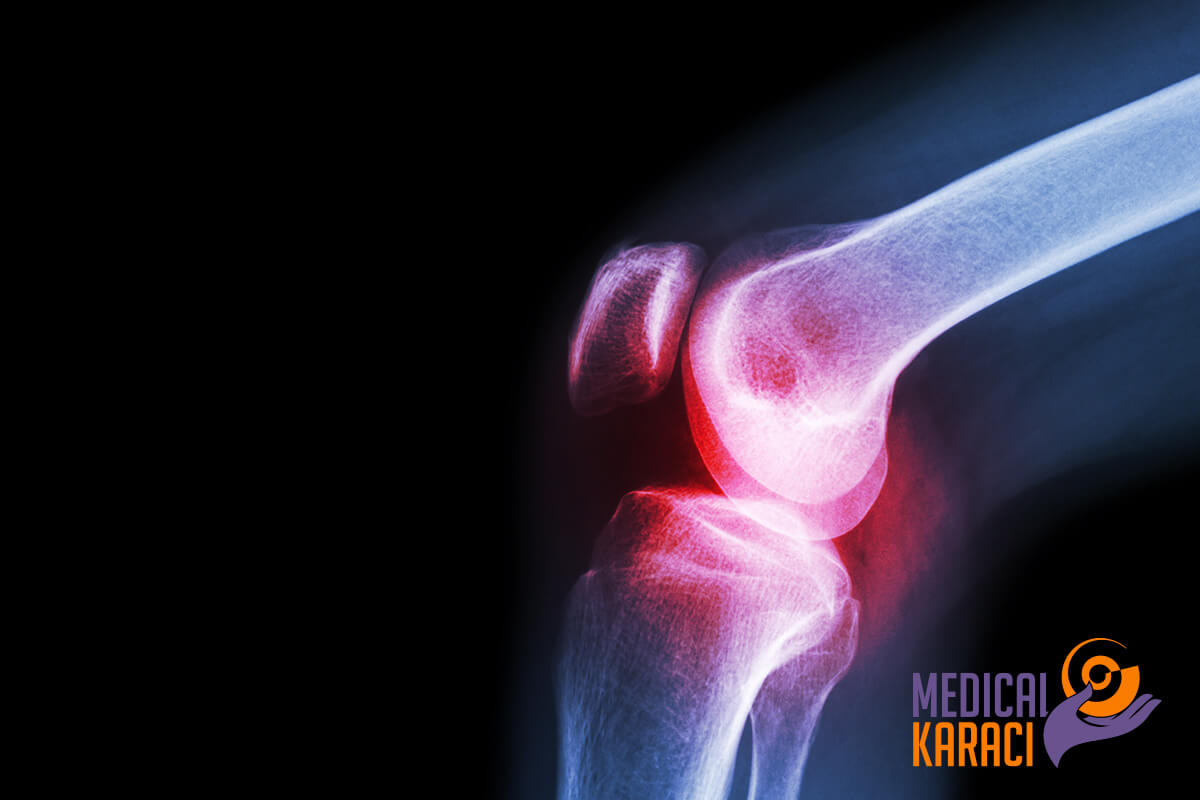

OSTEOARTRIT

L'osteoartrite è la forma più comune di artrite e colpisce milioni di persone in tutto il mondo. Si verifica quando la cartilagine protettiva che ammortizza le estremità delle ossa si consuma nel tempo.

Sebbene l'osteoartrite possa danneggiare qualsiasi articolazione, la malattia colpisce più comunemente le articolazioni di mani, ginocchia, fianchi e colonna vertebrale.

L'osteoartrite si verifica quando la cartilagine che ammortizza le estremità delle ossa nelle articolazioni si consuma gradualmente. La cartilagine è un tessuto duro e scivoloso che consente un movimento quasi privo di attrito delle articolazioni. Alla fine, se la cartilagine si consuma completamente, l'osso sfrega sull'osso. Ma oltre alla distruzione della cartilagine, l'osteoartrite colpisce l'intera articolazione. Provoca alterazioni dell'osso e il deterioramento dei tessuti connettivi che tengono insieme l'articolazione e collegano i muscoli all'osso. Provoca inoltre l'infiammazione del rivestimento delle articolazioni.